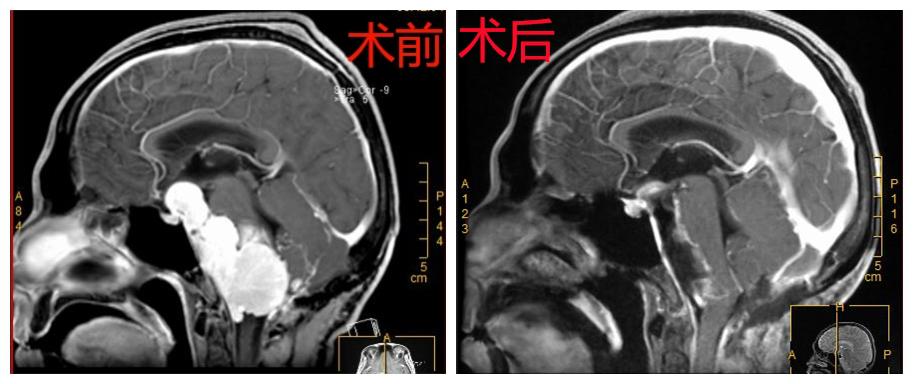

术前术后对比图

在尚未联系深圳市第二人民医院之前,曾先生病情急转直下,突然出现急性脑积水、高颅压、脑疝昏迷等症状,2018-04-01在当地医院急诊行“脑室外引流术”,然而这仅是权宜之计。曾先生家属根据北京天坛医院专家意见联系深圳市第二人民医院脑科中心医师后于2018-04-03转入我院,由神经肿瘤病区颅底组接收了曾先生。深圳市第二人民医院脑科中心主任、颅底肿瘤协作组组长蒋太鹏教授组织颅底组成员王建中副主任医师、林恒州副主任医师、左大辉主治医师、刘晓佳主治医师对曾先生病情进行全面评估发现,曾先生的复发肿瘤病理为“恶性孤立性纤维性肿瘤”,肿瘤目前已侵占右侧枕骨大孔区、桥小脑角区、斜坡、天幕及鞍上等部位,病变范围广泛,该肿瘤供血极其丰富。

因肿瘤生长区域有众多重要血管及颅神经通过,还压迫生命中枢脑干,解剖结构复杂,且既往有手术病史,肿瘤粘连严重,可能包绕各颅神经和重要血管,手术难度极大,术中极易损伤重要颅神经及血管,而且一次性完全切除肿瘤极其困难,术后也极易出现呼吸障碍、面瘫、吞咽障碍、昏迷、四肢瘫痪等严重并发症。对于医生来说这是一个非常棘手的病例,施行手术是一个极大的挑战。考虑到患者已辗转国内外多家医院均未得到有效救治,放弃手术即等于放弃生命,通过详细告知家属病情,家属表示积极配合治疗,在此基础上神经外科全体医师进行再次讨论,得到了神经外科首席专家高永中教授和全体医师的支持,并制定了详细的手术治疗方案及应急预案。

考虑到曾先生的脑室外引流管已留置3天,未来的3天为清明小长假,若等节后手术会增加颅内感染风险。随即蒋太鹏教授将患者病情通报手术室钮敏红、龚喜雪两位护士长及麻醉科杨新平副主任,她们表示全力配合为患者进行手术。时间就是生命,2018.04.05清明节放假第一天全体医护人员放弃休息,为曾先生施行手术。术中肿瘤供血极其丰富,在分离三叉神经和迷走神经周围肿瘤时曾出现“脑心反射”致患者心跳骤停,幸好丰富经验的手术团队及时处理,手术得以继续进行,历时约12小时,是一场不折不扣的拉锯战,对医师的精力、体力有极大的要求,手术顺利将肿瘤近全切除,将患者生命从死神的手中重新夺回。